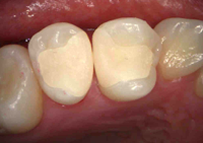

出来上がったセラミックスを試適後、歯にしっかりと接着し終了

以上、1〜2本の歯の治療では約1時間半程度でセラミックスの即日修復が可能となります。